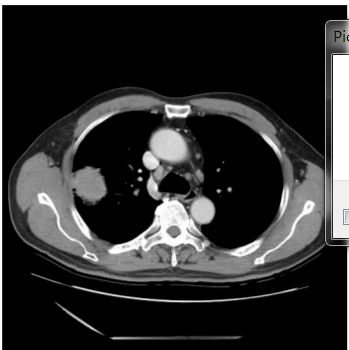

18. 67歲男性,過去無抽菸史,此次因發燒數日至門診就醫,胸部X光顯示右上肺實質化陰影,投予抗生素治療後無明顯變化,故安排胸部電腦斷層檢查(如圖),經支氣管鏡切片病理發現為肺腺癌。後來安排全身正子掃描以及腦部核磁共振,發現右上肺腫瘤的SUVmax為4.5,右下氣管旁淋巴結的SUVmax為2.7,此外無其他病灶。請問下一步最適當的處置為何? (A) 檢驗EGFR基因是否有突變 (B) 縱膈腔淋巴結切片病理檢查 (C) 手術切除 (D) 化學治療 (E) 同步性化學及放射線治療